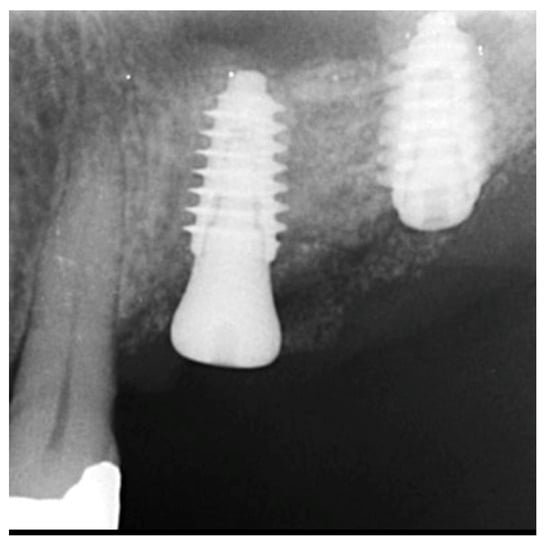

The patient returned at 10-weeks implant and graft placement and the soft tissue over the posterior quadrant was noted to be healed with no inflammation present (Figure 10 left). Following local anesthetic administration a full thickness flap was elevated and the previously grafted 2nd molar crestal area was filled with immature host bone (Figure 10 right). A radiograph was obtained, which noted a crestal height of 7.1 mm present (Figure 11 left). The 2nd molar site was prepared in a similar fashion as previously detailed, utilizing Densah burs to osseodensify the area and accomplish a crestal sinus augmentation and a 5 × 8.5 mm Anyridge implant was placed (Figure 11 middle and right). An impression of the 1st molar implant was obtained to initiate its restoration while the 2nd molar implant was integrating. A healing abutment was placed on the implant at the 1st molar and a cover screw on the 2nd molar implant and a radiograph obtained to document the clinical result to date (Figure 12).

Figure 11.

Radiograph demonstrating sufficient height of the ridge to allow primary stability of an implant placed at the 2nd molar with a crestal sinus augmentation at 10 weeks of graft healing (left), site preparation for the crestal sinus augmentation (middle) and implant placement into the site (right). Green line is the measurement of the height of the bone at that point between the crest and the sinus floor.